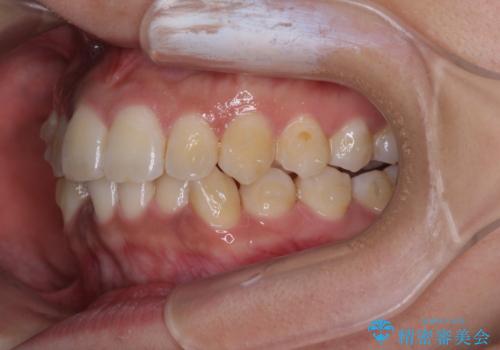

前歯のデコボコと隠れてしまう下顎前歯 インビザラインですっきりと改善

- 前歯のデコボコと、深い咬み合わせにより前歯が隠れていることを気にして来院された患者様です。

海外に長期滞在する予定があるとのことで、インビザラインにて矯正治療を行うこととしました。

インビザライン発注後に長期滞在先から2年間ほど帰国することができず、インビザラインの有効期限内に終了できるのか不安でしたが、矯正治療開始後は十分な装着時間を達成され、1年未満の期間で無事に終えることができました。